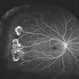

- macula serpiginous choroidopathy, Optos, fundus autofluorescence (FAF), macula lesion, ultra-wide field imaging, fundus photograph

- Optos ultra wide field auto fluorescent image of 20-year-old female presenting with serpiginous choroidal atrophy. Patient was unaware of vision loss OD, until accidentally covering OS and noticing the change. Acuity of 20/200 OD and 20/15 OS at time of imaging.